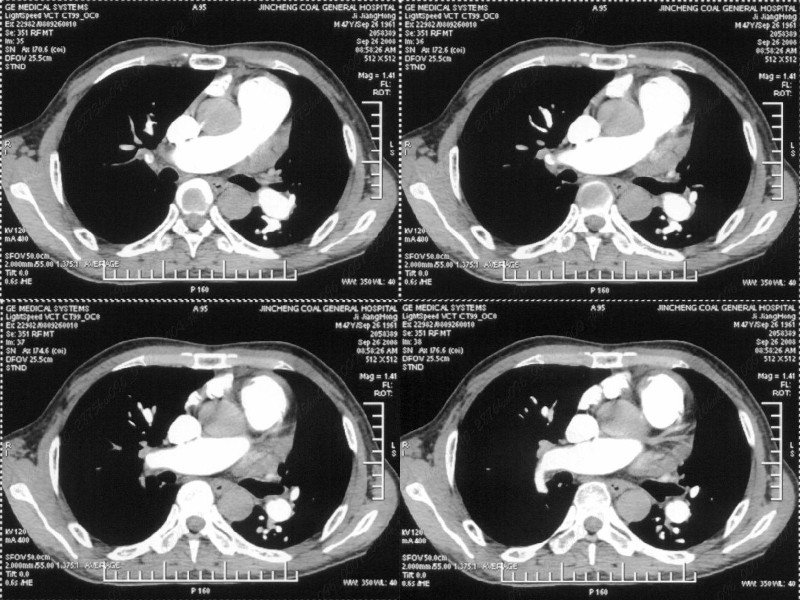

男性,47岁。胸部不适一年,ct检查发现右胸膜下结节。http://www.radida.com/bbs/forum.php?mod=viewthread&tid=46094

考虑心脏疾患引起的右侧斜裂增厚。

右肺静脉充盈缺损,左心房体积小,右肺动脉远端动脉充盈缺损,右肺血管影细小,考虑;右肺动脉远端栓塞.

右肺中叶外侧段占位,考虑周围型肺癌伴局限性肺气肿,不除外炎性假瘤